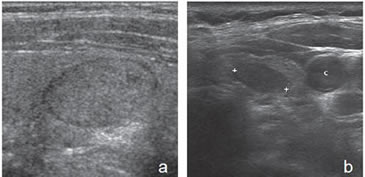

encapsulado (flecha abierta). Otra apariencia típica es la de un nódulo no encapsulado, que contiene múltiples espacios anecogénicos (coloide), separados por finos septos, que le da un aspecto espongiforme (Figura 18a) o en “panal de abejas”7. Los espacios quísticos pueden ser de tamaño variable, y observarse focos hiperecogénicos en las aéreas quísticas que contienen coloide o focos ecogénicos lineales en las interfases entre los espacios quísticos y los tabiques o la pared; pueden ser hipo, iso o hipervasculares.

Los componentes quísticos pueden ser muy pequeños y sólo detectarse con equipos de alta resolución. Este aspecto espongiforme puede aparecer más acentuado cuando los espacios quísticos son de mayor tamaño; si aparece hipervascularizado, a simple vista puede simular una neoplasia quística (Figura 18b y c). Puede predominar el componente quístico, y sin embargo, el componente sólido conservar el aspecto espongiforme (Figura 18d).

Figura 18. a) Tres nódulos coloideos, con aspecto

espongiforme, isovasculares al “doppler color”.

La flecha indica un espacio quístico y la flecha

abierta indica un pequeño tabique hiperecogénico.

La alternancia de ambos, forma este aspecto

en “panal de abeja”; b) y c) Nódulo coloideo

con aspecto espongiforme, con espacios quísticos

de mayor tamaño, de forma redondeada, que

aparece hipervascularizado en las áreas sólidas;

d) Nódulo coloideo mixto, predominantemente

quístico, en que el componente sólido conserva el

aspecto espongiforme (flecha abierta).